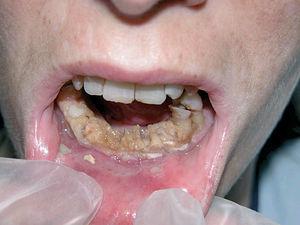

La paciente tenía una temperatura corporal de 38,6 °C, su estado general estaba afectado y presentaba una lesión ulcerada, necrótica y maloliente de unos 3 cm de diámetro en vestíbulo, encía y mucosa labial inferior (fig. 1). La lesión, cubierta por una seudomembrana marronácea, había provocado la pérdida de los tejidos de soporte paradentales con avulsión espontánea de los incisivos inferiores, movilidad importante de los caninos inferiores y exposición del hueso alveolar.

Figura 1. Lesión ulcerada y necrótica de unos 3 cm de diámetro en vestíbulo, encía y mucosa labial inferior. Exposición de hueso alveolar.